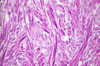

MDx

Atrophy